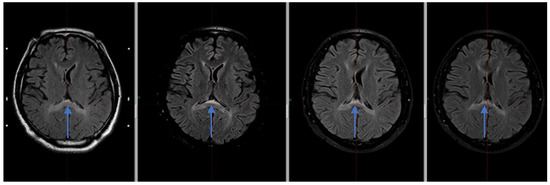

Figure 2. Hyperintense signal within the splenium of corpus callosum visible in the MRI FLAIR sequence in subsequent MR examinations—from the left: 12.2019, 06.2020, 12.2020, 01.2022 (blue arrows).